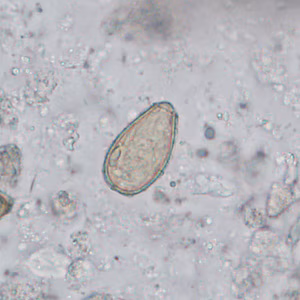

Case #402 – August 2015

A stool specimen was collected from a 28-year-old man from China as part of a refugee health screening program. The stool was collected in 10% formalin and a formalin-ethyl acetate (FEA) concentration was performed. A wet mount smear was prepared from the sediment and examined for parasites. Figures A–C show what was observed at 400x magnification; the objects of interest measured 25-30 micrometers long. What is your diagnosis? Based on what criteria?

Figure A